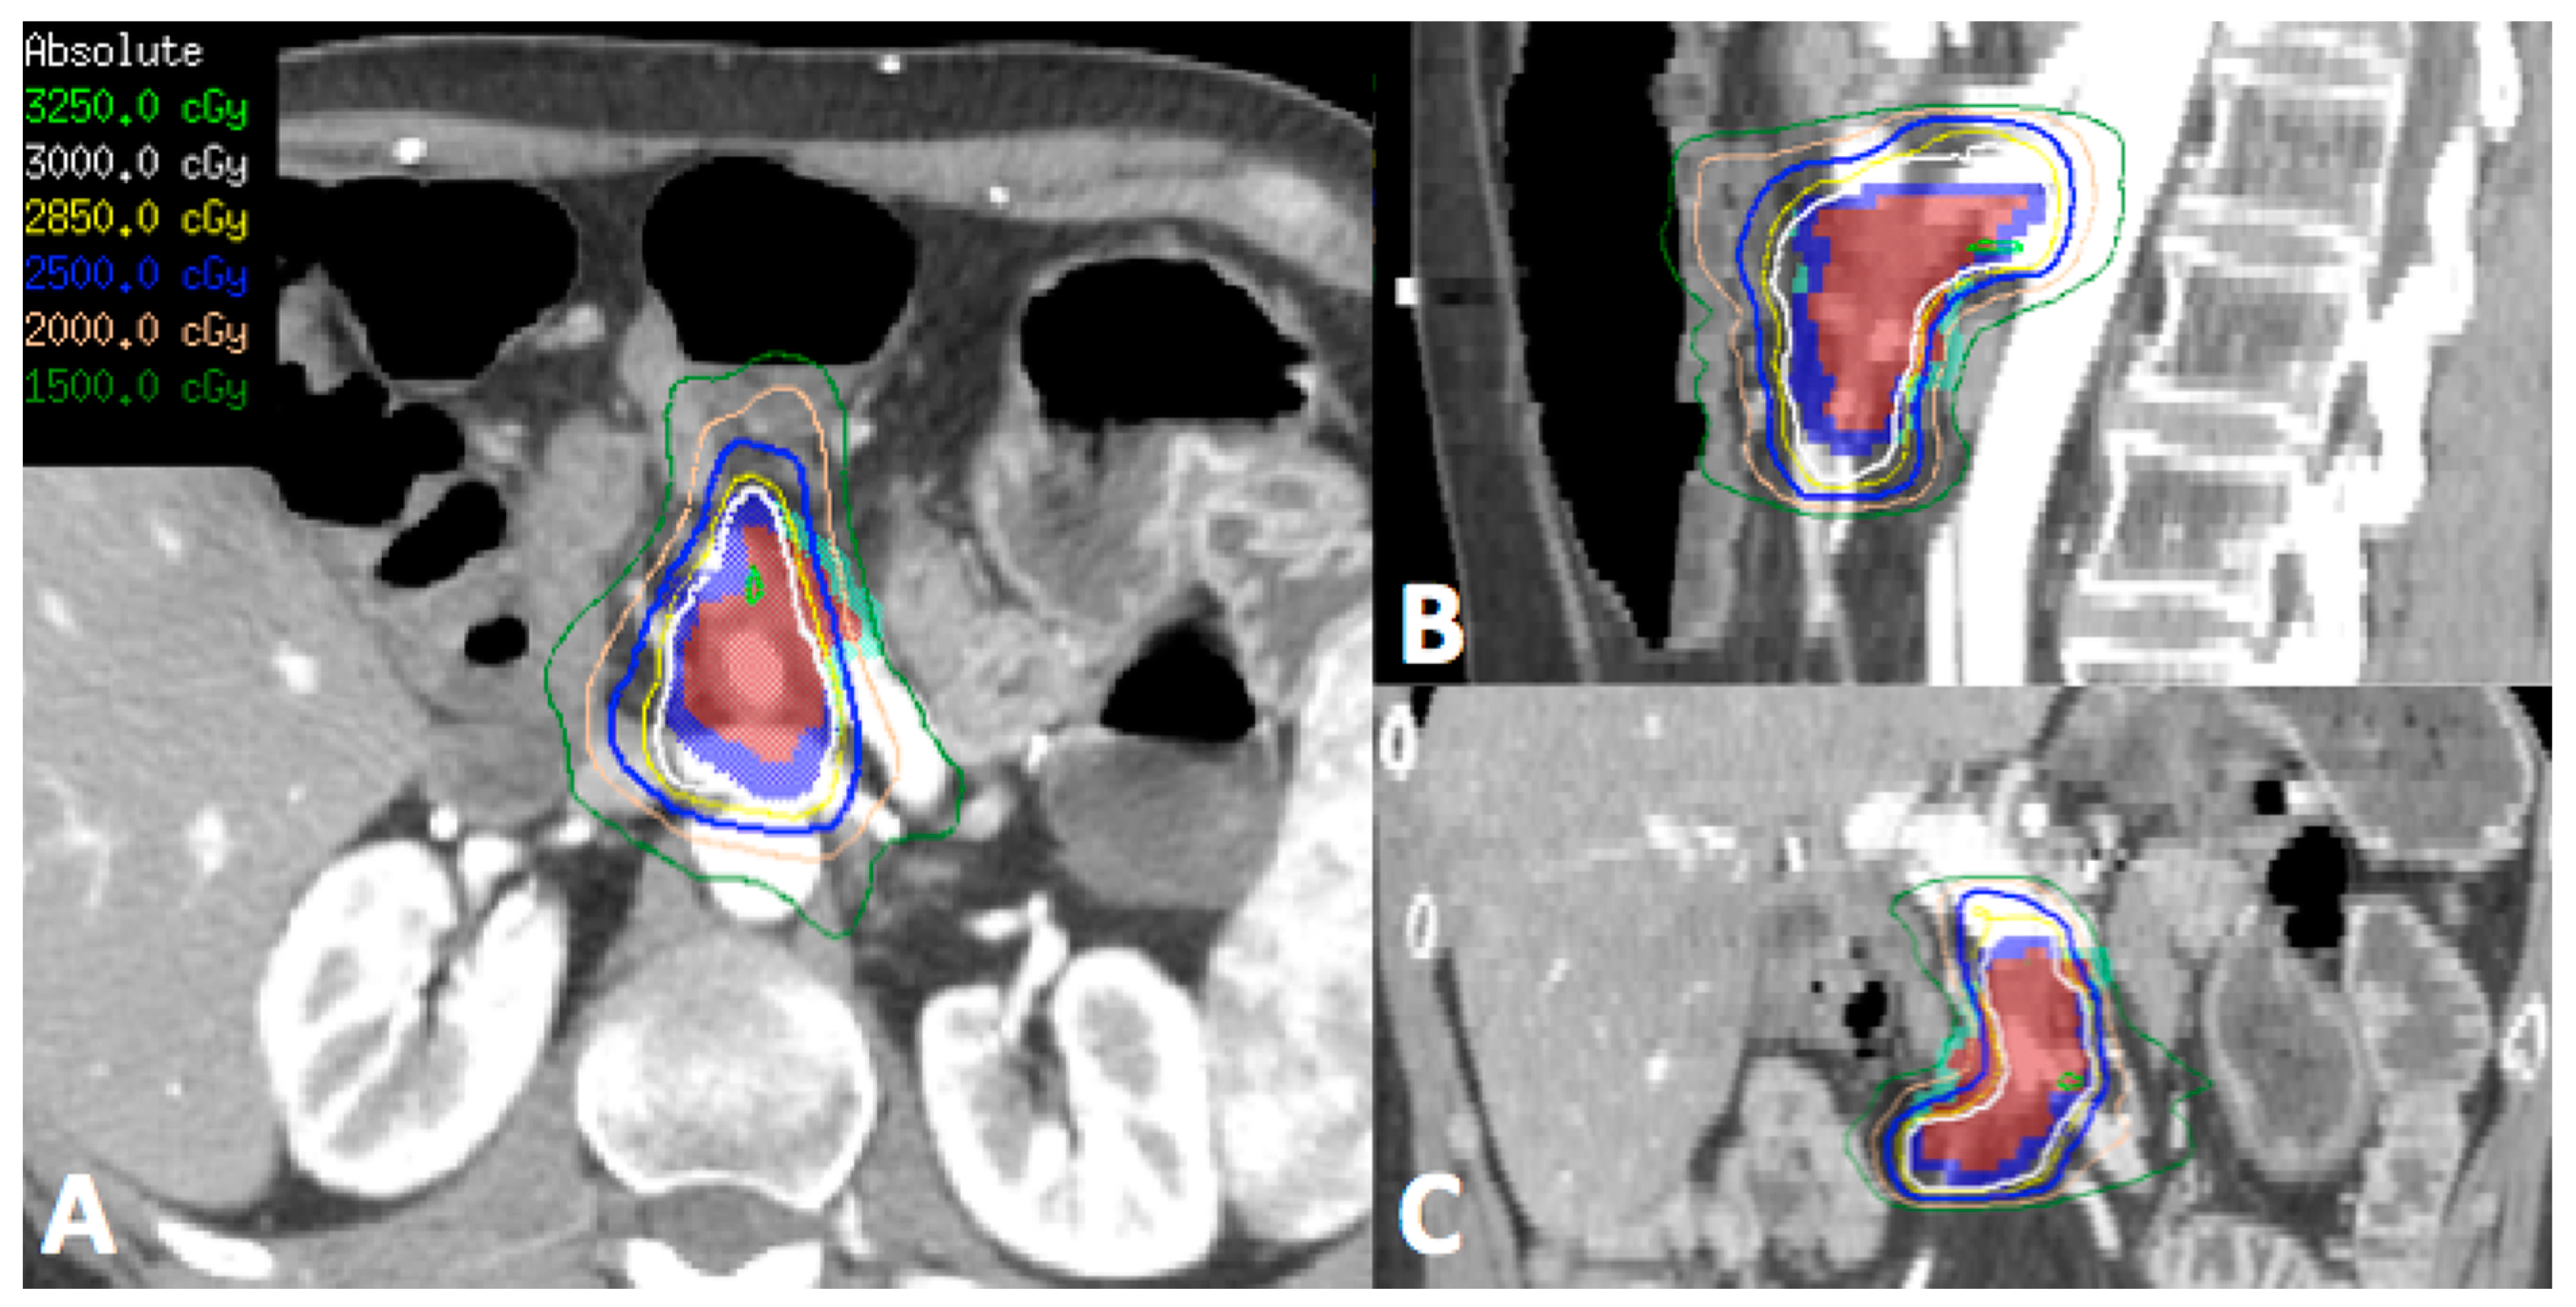

In patients who have had previous radiotherapy, it is imperative to obtain previous treatment plans to assess dose in relation to surrounding normal structures, in particular the duodenum, small bowel and stomach (Figure 1). Reirradiation in this setting could potentially cause significant late effects, depending on the cumulative doses to the normal structures. SBRT is becoming increasingly accepted when patients are considered for reirradiation in the attempt to maximize dose to the tumor whilst limiting the dose to surrounding normal organs thereby reducing the risk of significant late effects.

Figure 1.

Representative transverse (A), sagittal (B) and coronal (C) images of the reirradiation treatment plan using stereotactic body radiotherapy (SBRT) for a patient who had previous 3D conformal radiotherapy to the region 5 years ago to 50.4 Gy in 28 fractions. (Red—gross tumor volume, Dark blue—target for 30 Gy, Light blue—target for 25 Gy due to proximity to surrounding bowel and stomach). Patient tolerated treatment well with Grade 1 nausea and was alive 12 months post-treatment with no significant late toxicity.

SBRT is potentially a feasible and safe option in patients with local recurrence. Table 2 summarizes the studies where SBRT was utilized in the setting of local recurrence with the majority of publications on patients who received previous radiotherapy. As this group of patients is small, the evidence is limited to retrospective studies alone. Nevertheless, from Table 2, SBRT can achieve good local control (1-year freedom from local progression of 62–91%). Although the incidence of grade 3 or higher late toxicity is rare, great care should be taken at treatment planning and delivery with regards to the stomach and bowel dose as gastrointestinal toxicity may cause significant morbidity to this group of patients with limited life expectancy.